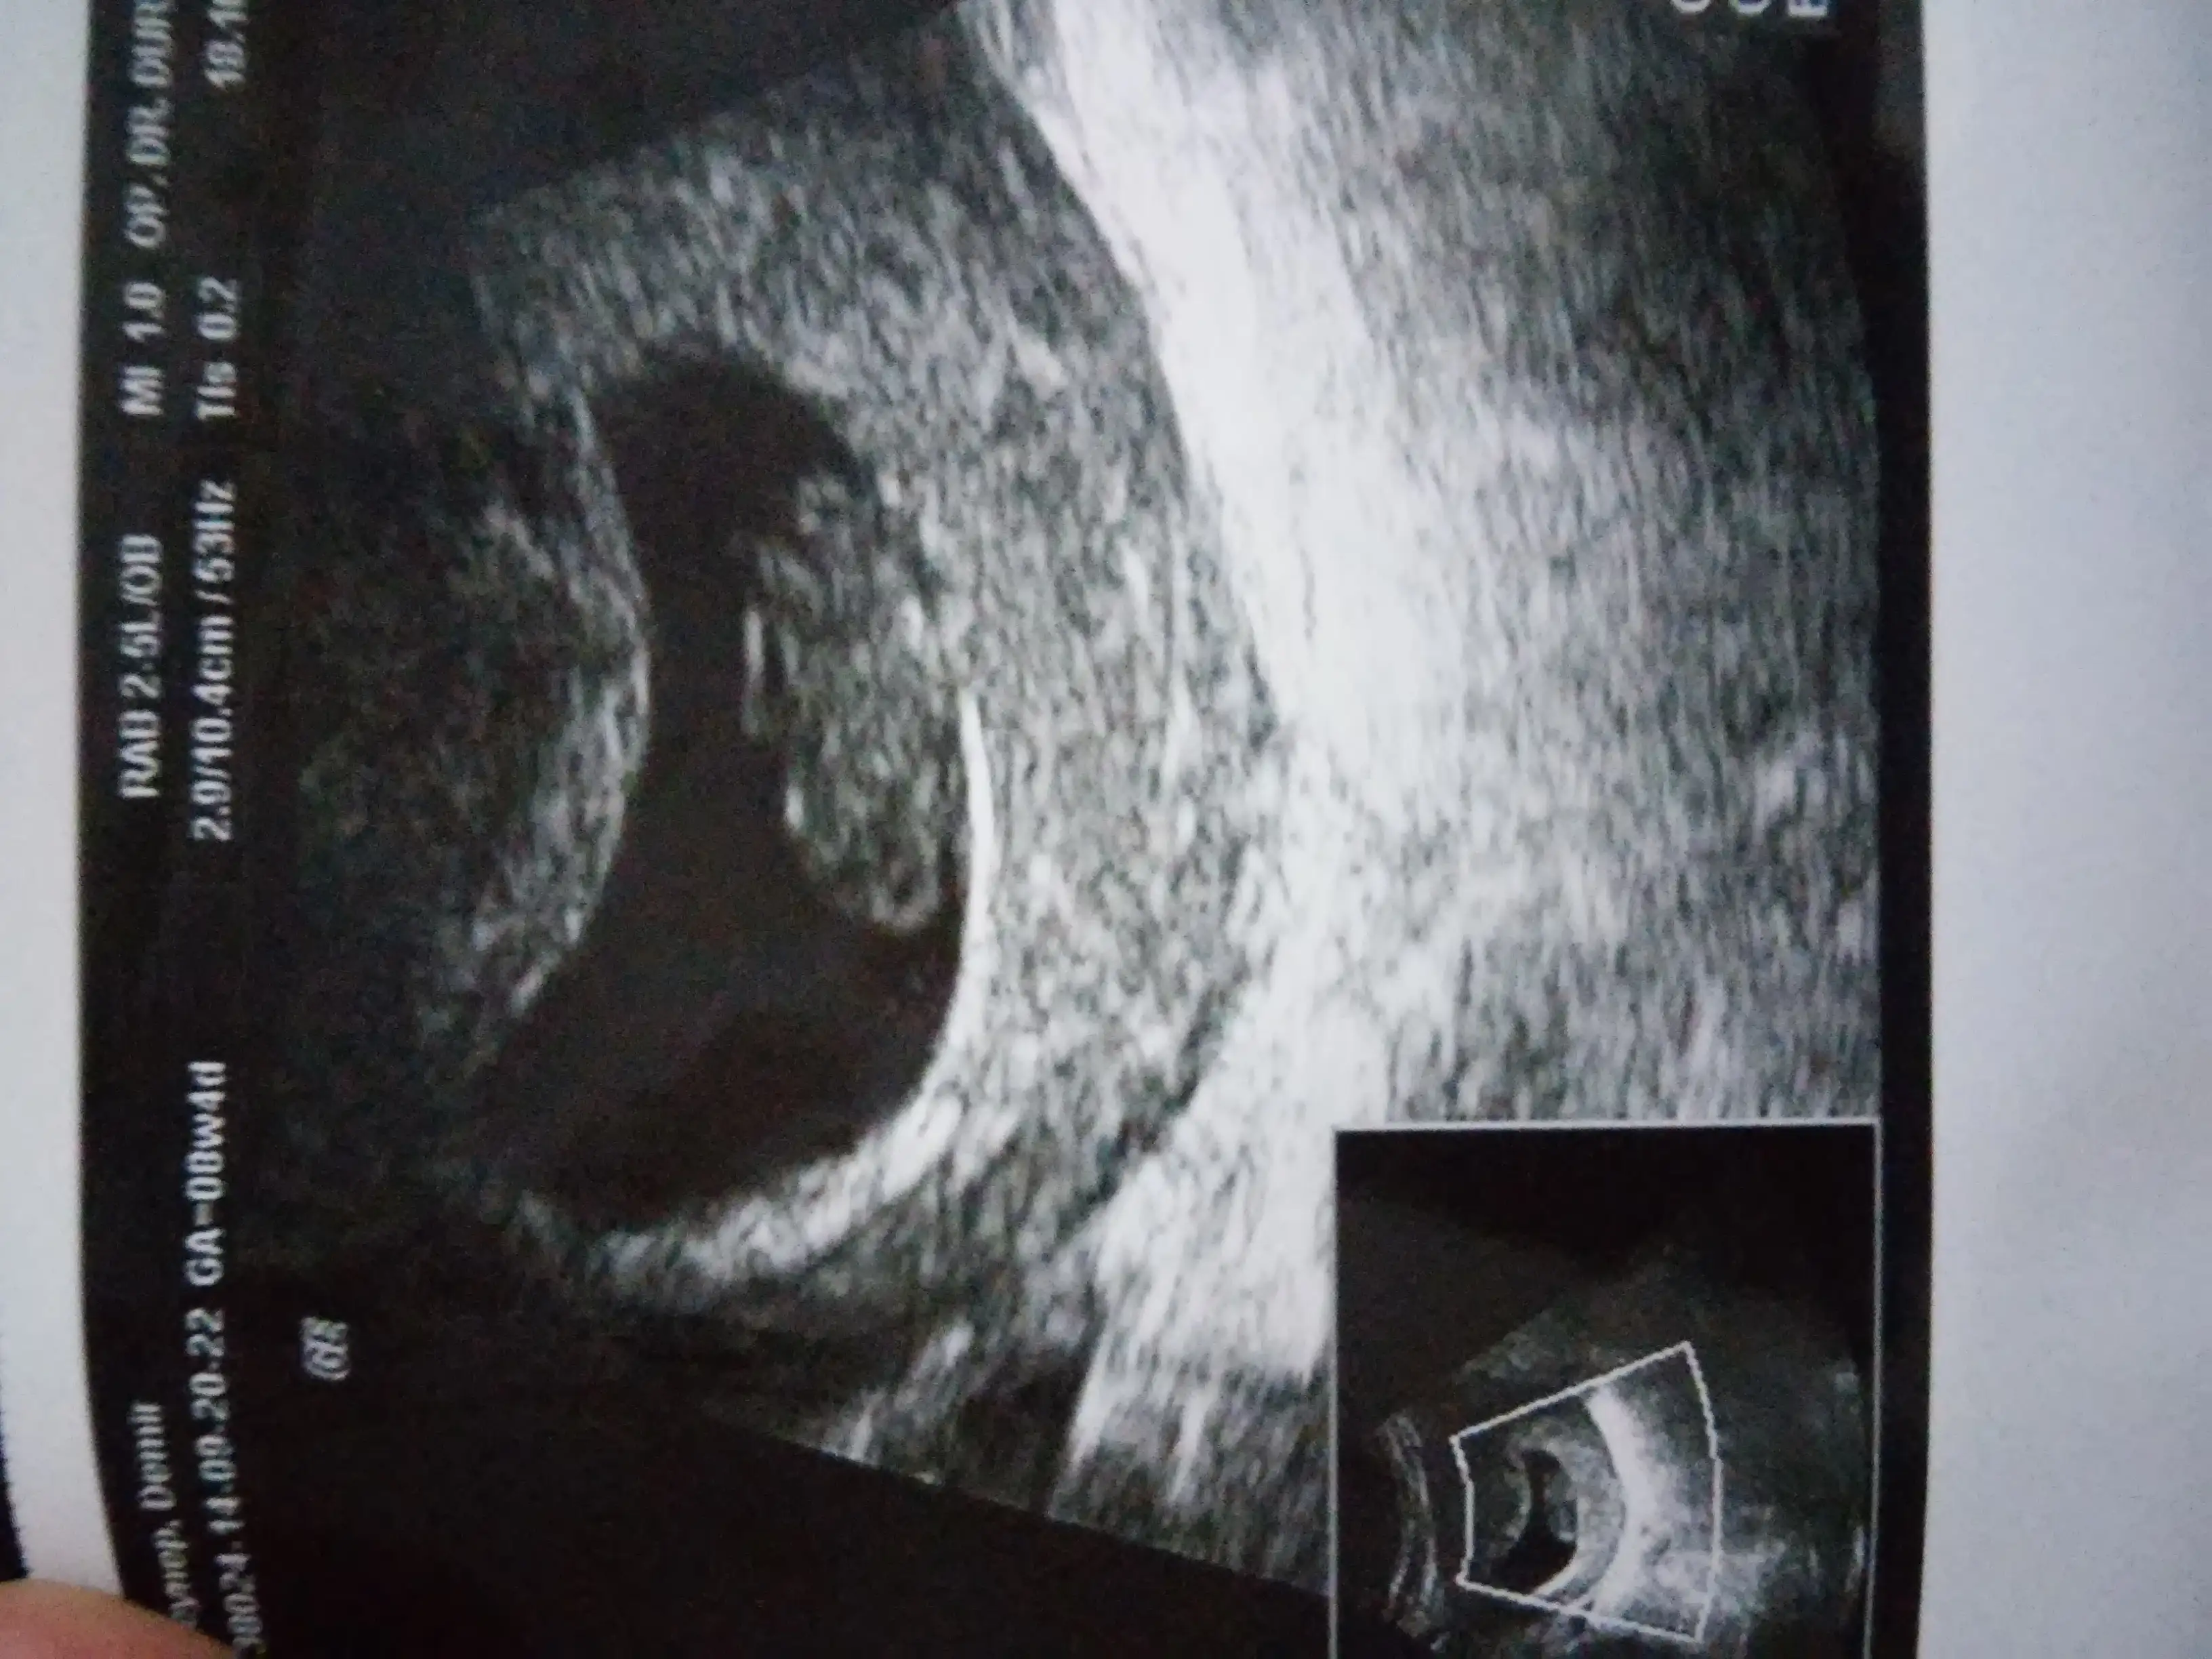

erkek bence ayrıca bu grubun tecrübelilerinden zeynepnazz da erkek hemde yüzde yüz erkke dediKızlar merhaba benim bebeğime de yorum yapar mısınız? Ve face te grup varsa bende katılmak isterim yaaa ismi varmı? Benim bebeğim burda 12+1 doktorun tahmini var ama 16 haftada söyleyeceğim dedi bide siz bakın lütfenn :)

face de grubun adı nub teorisine göre cinsiyet ama ayarları gizliye çevrilmiş bulunamıyo bazenKızlar merhaba benim bebeğime de yorum yapar mısınız? Ve face te grup varsa bende katılmak isterim yaaa ismi varmı? Benim bebeğim burda 12+1 doktorun tahmini var ama 16 haftada söyleyeceğim dedi bide siz bakın lütfenn :)